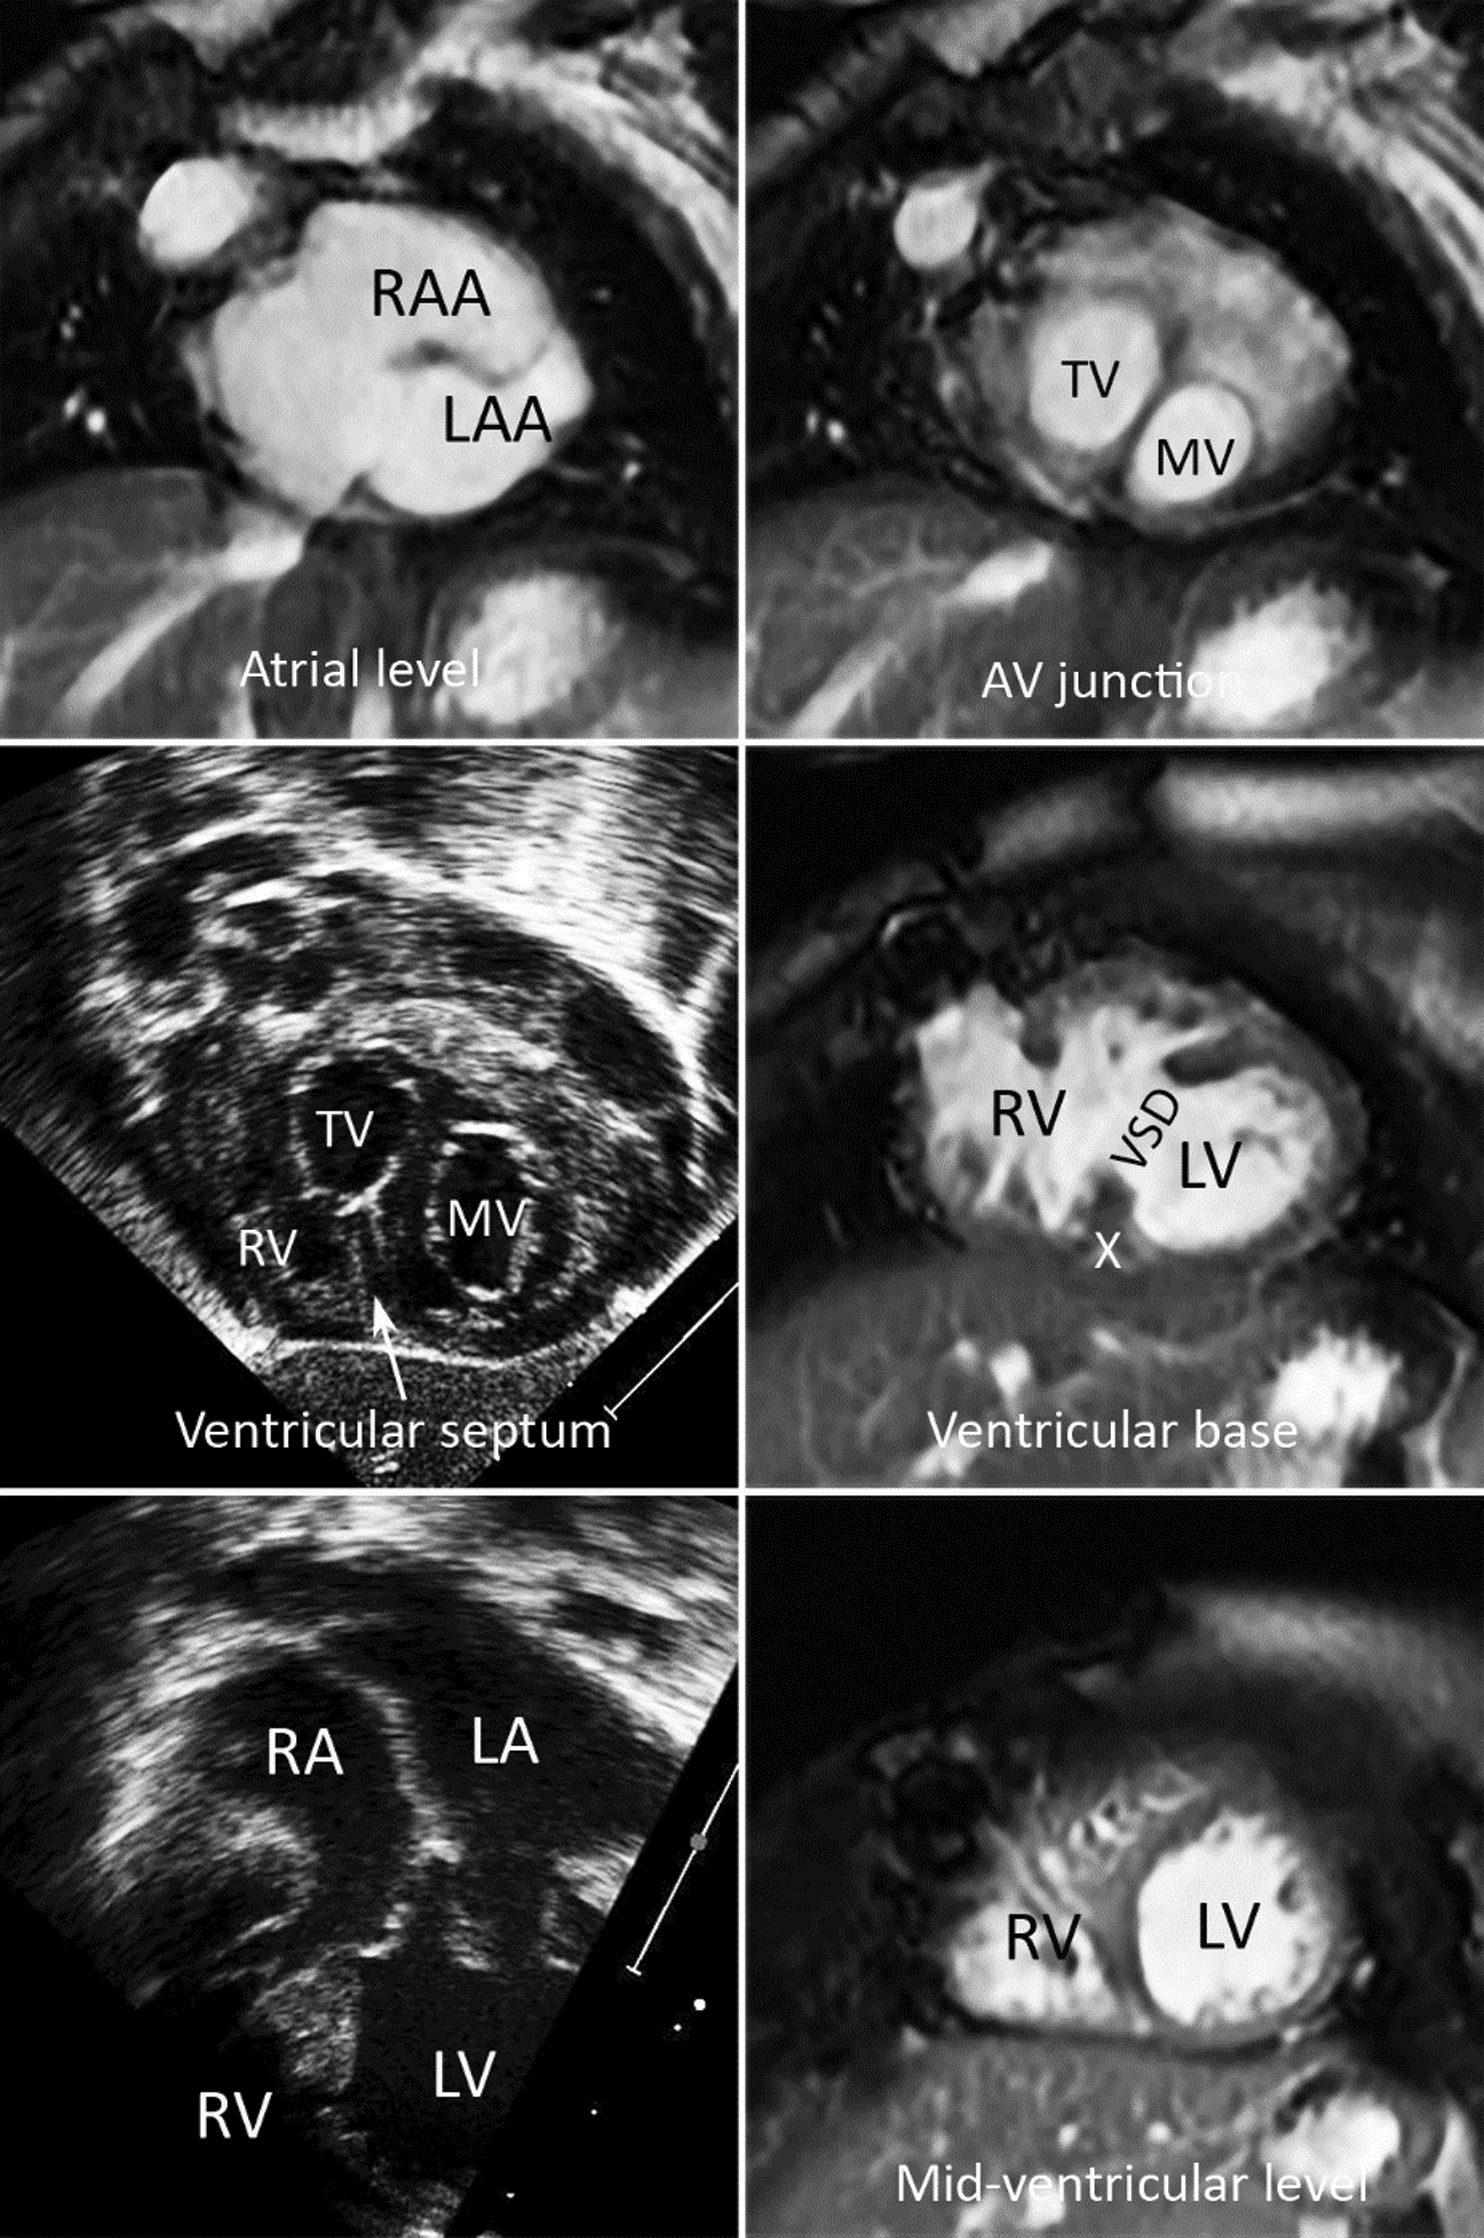

There was a mild degree of atrial-ventricular septal malalignment with the tricuspid valve displaced upward and slightly leftward in relation to the mitral valve in all (Fig. 5). As a consequence, the atrioventricular valves with the adjacent atrial septum appeared rotated clockwise as seen from the apex.

There was mild overriding of the anterior medial part of the tricuspid valve through the VSD involving the anterior aspect of the inlet part of the septum. The VSD did not reach the crux cordis in any of these patients. The posterior interventricular groove was aligned with the atrial septal plane at the crux cordis in all. Two had chordal insertion of the overriding tricuspid valve to the ventricular septal crest. No patient had overt straddling of the tricuspid valve. The tricuspid valve was hypoplastic in 3. The ventriculoarterial connection was double outlet right ventricle with the outlet septum free floating in the right ventricular outflow tract in 6. Two had discordant ventriculoarterial connection with pulmonary valve atresia.

Figure 5: Short-axis MR images and echocardiograms in coronal and 4-chamber planes (lower two panels on the left) from a patient with left juxtaposition of the atrial appendages. The atrioventricular (AV) junction appears rotated clockwise as seen from the apex. The atrial septum is malaligned from the plane of the ventricular septum. Echo images show mild overriding of the tricuspid valve. The VSD involves the anterior part of the inlet septum and does not reach the posterior interventricular groove (X). LA, left atrium; LAA, left atrial appendage; LV, left ventricle; RA, right atrium; RAA, right atrial appendage; RV, right ventricle

Echocardiograms were far superior to MRI in demonstration of the chordae tendinae and their insertion sites (Figs. 4 and 5). On the other hand, it was much easier and objective with CMR than with echocardiograms to characterize the septal malalignment (Figs. 2, 3 and 5).